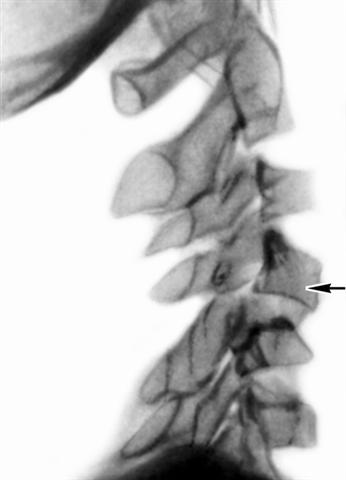

Рис. 8. Рентгенограмма шейного отдела позвоночника (боковая проекция) при переломовывихе пятого шейного позвонка: сместившийся позвонок указан стрелкой.